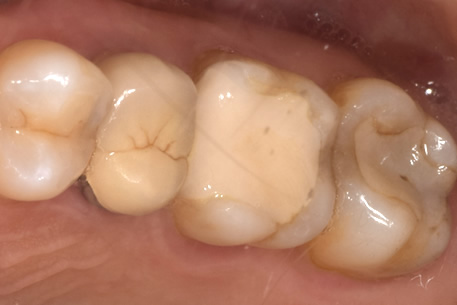

治療中

治療中①

治療中②

治療中①:つめ物をとったところ。茶色い部分は虫歯になっている。

治療中②:染色液を用いて虫歯を選択的に取り除いた。歯はかなりなくなっており、神経近くまで進行していた。

経過観察

虫歯を取り除いた後、神経を守るためのお薬をつめて、2ヶ月ほど経過観察をした。

治療後

経過観察中に症状がでなかったため、セラミックのつめ物をいれていった。